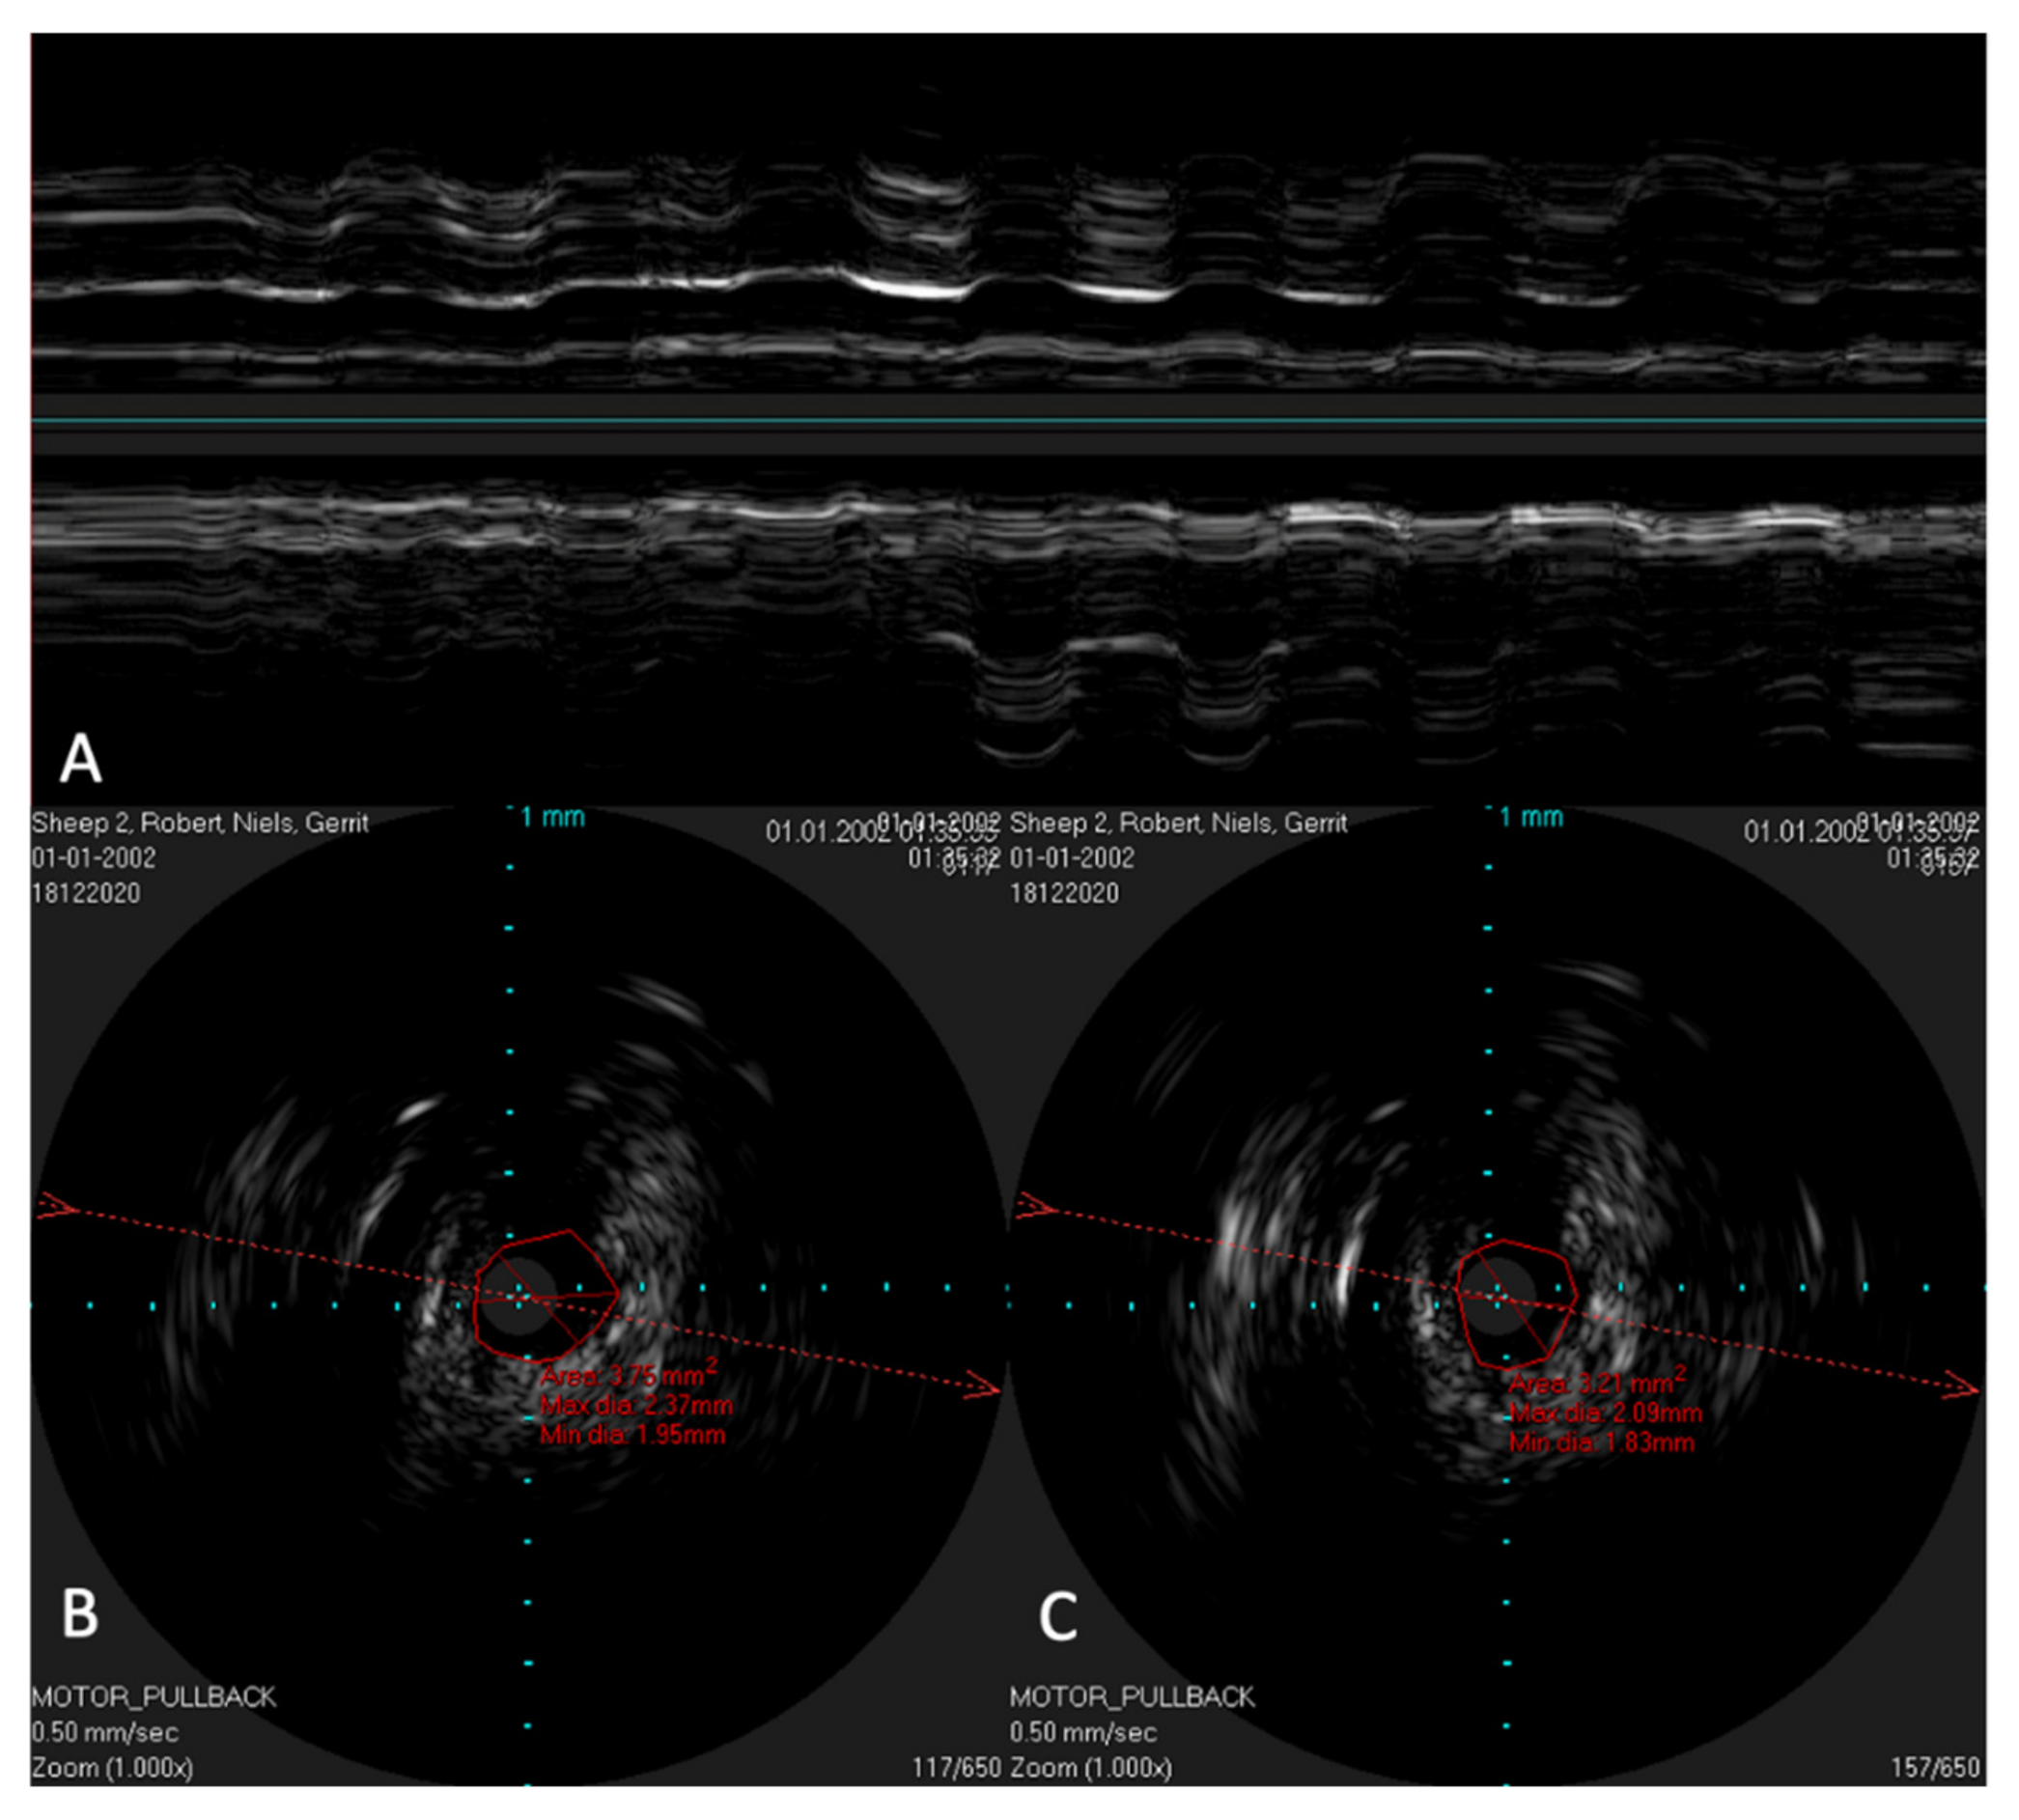

The reconstructed longitudinal view of the IVUS scans, as shown in Figure 4 with the corresponding circular views, was then compared with the 3D model and the corresponding histological sectional images of Schuon et al., 2021 [24] (Figure 5). Based on this, the surrounding structures could be identified in the IVUS image.

Figure 4. Longitudinal image of the ET with the corresponding cross sections. (a) near the ET isthmus. (b) in the middle section of the ET. (c) near the pharyngeal ostium. Bone is marked with *. The bony structures represent consistent topographic landmarks. The cartilage of the ET shows low echogenicity (white arrows). Note that the dashed red line in the cross-sectional image represents the axis of the longitudinal image. The tip of the arrow points toward the lower part of the longitudinal image.